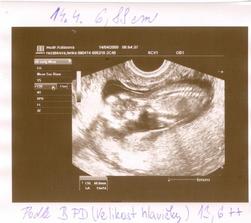

*****3.3.2009 nás čeká první poradna -------> První návštěva u nové dr. dopadla báječně.Viděla jsem miminko, i jeho srdíčko,které blikalo jako o závod.Měříme 7,4 mm.***** Další poradna 20.3.2008***** 5.3 mě začali trápit těhu nevolnosti.Brrrr,nikomu to nepřeju.*****10 tt (19.3.2009) - pomalinku začínáme nakupovat výbavičku,aukce jsou docela adrenalinovej sport 🙂)))*****20.3.2009 - Kontrola u dr,Utz,máme 3,03 cm,takže upraveno stáří těhotenství na 9+6 tt,ne 9+2 tt. Na UTZ jsem nádherně viděla mimiškovo ručičky i nožičky.Paní doktorka mi dokonce celý UTZ nahrála na flasch kartu,takže na mimíse můžu koukat i doma.Dostala jsem těhu průkajdu a cestou domů jsem zase mimísovi za odměnu něco koupila.***Oznámeno rodině maminky.Tatínkovo rodina se to dozví cca 30.3.09.-*****30.3.2009 Dnes přišla na návštěvu miláčkovo maminka.A jelikož měla 20.3. narozeniny pojali jsme velké oznamování jako dárek.Koupily jsme lahvinku červeného,kyti a přáníčko.Do obálky za přáníčko jsme nastražily řidičák na kočárek a fotečku z UTZ.Když jsem jí předávala přáníčko,řekla jsem jí,aby se na to raději posadila.A jak mamča vytahovala přáníčko vypadl na ní ten řidičák.Na něj koukla:´´Hm,řidičák na kočárek????????´´Pak koukla na nás.´´To jako,že čekáte ????????´´ a já se jen uculila,na nic jinýho jsem se nezmohla.No a nastávající babička na to´´No ještě,že jsem si na to sedla´´*****6.4.2009 - Koupen kočárek (Naštěstí nejsme pověrčivý a tak výhodná koupě by se už nemusela objevit.),vanička a polohovací lehátko.*****Třetí poradna ---- 14.4.2009 - Tlak máme v pořádku,na váze jsem se trochu zděsila 59,5 kg,tj. +7 kg,ale paní doktorka nic neříkala.Při UTZ jsem si poplakala viděla jsem ručičky ,nožičky,5 prstíků,nosní kůstku.

CRL je 6,88 cm,tj. 13+1 tt ---

FL je 0,9 cm,tj. 12+5 tt (délka stehenní kosti) ---

BPD je 2,2 cm,tj. 13+6 tt (Hlavička od ucha k uchu).Prý máme přímo ukázkový miminko.Jsem ale absolutně zmatená,jak je to naše štěstíčko vlastně starý.*****6.5.09 - Dnes jsem byla u dr zase na kontrole,tentokrát šla se mnou dcerka.Tlak super,váha 61,5 kg,takže ofiko 9 kg nahoře.Na dnešní kontrolu UTZ v plánu nebylo,ale když se přišla podívat starší sestra,tak jí paní doktorka miminko ukázala.Ručičky,nožičky,tělíčko a hlavičku a malá byla spokojená jako blecha.I z tohoto kratičkého vyšetření máme fotečku.A dnes bylo UTZ poprvé přes bříško.Sestřičkám jsem darovala 3 zkumavky krve:Na Downův syndrom,rozštěpy a na mojí žádost i na toxoplazmozu,na výsledky si mám volat 15.května..Dostala jsem doporučení na internu,na genetický UTZ do NATALARTu.Další kontrola až 4.6,ach jo.A dnes jsem konečně objednala můj vysněnej přebalováček.*****Od 2.5.2009 - -16+3 tt - naše štěstíčko o sobě konečně začalo dávat vědět.Opírá se mi o bříško zevnitř,pohyby jako takové ještě necítím,ale tlačí mě někdy dost silně.Tlaky se objevují denně,takže jsem si jistá,že je to náš poklad.******13.května 2009 - Jsem nedočkavec,tak jsem už dneska zkusila zavolat na výsledky testů krve a výsledek?ČEKÁME ÚPLNĚ ZDRAVÉ MIMINKO,HURÁÁÁÁÁÁÁÁÁÁÁÁ****** 26.5.2009 - 19+6 tt Dnes mě naše miminko poctilo 1 pořádným kopancem,do dneška to bylo jen takové lechtání a tlaky na břišní stěnu.*****2.6.2009 - Dnes jsme byly na velkém UTZ,vážíme cca 370 g a čekáme zdravou HOLČIČKU.****4.6.09 - Další kontrola u dr.Váha 66 kg,tzn +13,5 kg.Jaterní testy i laboratoř v pořádku,tlak super.Jen mám bílkovinu v moči.*****16.6.2009 - Dnes jsem byla na testu na cukrovku.No a jak to dopadlo,tak moc mi to chutnalo,že jsem se pozvracela.Doktorka mě na to naštěstí znova nepožene.Je fakt zlatá.*****Další poradna 4.7.2009 - 25 tt **** 28.6.2009 - 24+1 tt - Dneska se naše malinká rozkopala tak,že si začínám myslet,že bude kopat za nároďák.Už to nejsou ty ojedinělé kopance,ale kope do mě třeba 2 hodiny v kuse.Někdy je to nepříjemné,ale aspoň o cácorce vím a už se tolik nestrachuju,jestli je v pořádku.*****Kontrola ve 25 tt -2.7.09 - Tak jsem sice dneska na kontrole sice dostala prenatal box,ale radost z toho vůbec nemám.Mám asi nejspíš zánět močáku,protože mám nějakou potvoru v moči,takže se mám prolejvat urologickým čajem.